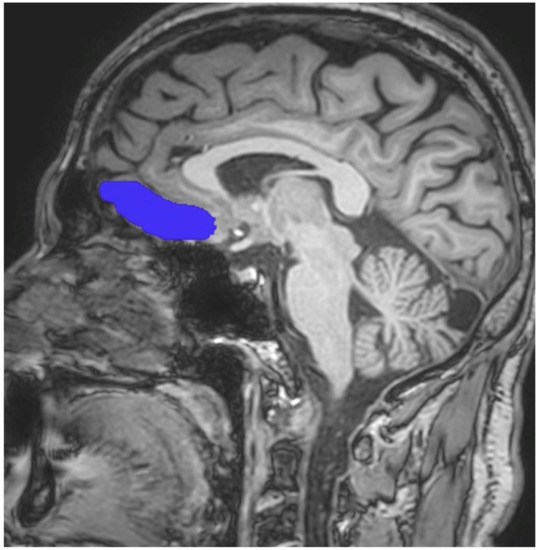

Image analyses were carried out using the FreeSurfer program (version 4.4), a free program to use and available to download online, which was used to reconstruct the cortical surfaces and detect the cortical thickness from magnetic resonance images (http://surfer.nmr.mgh.harvard.edu, accessed on 10 November 2022). For all processes, the method of Epstein et al. was followed [39]. The process utilised to analyse each subject’s brain images is available on the FreeSurfer website. Scans were processed by a radiologist who was blind to both the diagnosis of patients with alcohol use disorder and to whom was a patient or a healthy control subject. The process included motion correction, extraction of the brain tissue, transformation to Talairach space, segmentation and parcellation into the OFC region as described by Desikan et al. [40]. After this process, scans were also examined by a senior radiologist (M.K.) to ensure that segmentation and parcellation were performed correctly. In addition, scans were also reviewed for the presence of any artifact. However, no artifact was found. Uncorrected OFC cortical volumes (mm3) were divided by the total segmented brain volume (mm3) and then multiplied by 1000, to obtain the corrected cortical volumes. In contrast to Epstein et al.’s study, the OFC region was investigated in two parts, as left and right OFC [39]. Assistance was obtained from standard neuroanatomy atlases during all measurements [41,42,43]. On the other hand, the boundaries of the OFC region were adapted from Portas et al. and Riffkin et al. [44,45]. By using those guidelines, the same procedure as in our previous studies was preferred [46,47]. When determining the volumes of the OFC, the superior boundary of the OFC was defined by a line extending from the anterior commissure to the posterior commissure. The point at which the olfactory sulcus first appeared was determined as the posterior landmark. As expected, while the inferior boundary of the OFC was selected the most inferior aspect of the cortex, the most lateral edge of the brain cortex was also accepted as the lateral boundary of OFC. Finally, the longitudinal fissure was accepted as the medial boundary of the OFC. Sample imaging owing to the OFC is presented in Figure 1, whereas the images obtaining from the Freesurfer program are presented in Figure 2.

Figure 2.

Sample cortical thickness measure for the OFC.